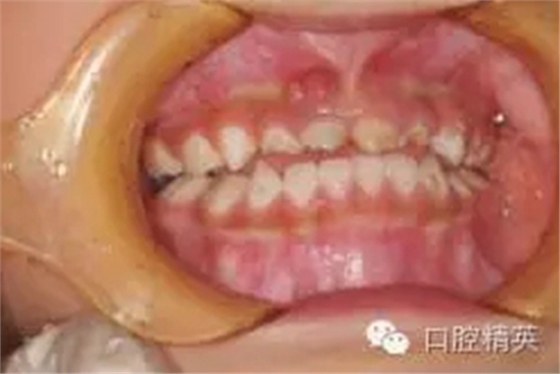

臨床檢查:頜面部及頸部未見明顯異常。口腔衛(wèi)生狀況尚可, 52,61,62,63,73唇舌面齲,54,64,74,84牙合面齲壞,腐質(zhì)中等,叩(-),松(-),牙齦未見明顯異常;75牙合面深齲壞,大量軟腐,叩(-),松(-),牙齦未見明顯異常,腐質(zhì)未去凈見露髓孔;51大面積齲壞,大量腐質(zhì),叩(+),松(Ⅰ),唇側(cè)牙齦可見5mm×6mm的包,軟;余牙未見異常。